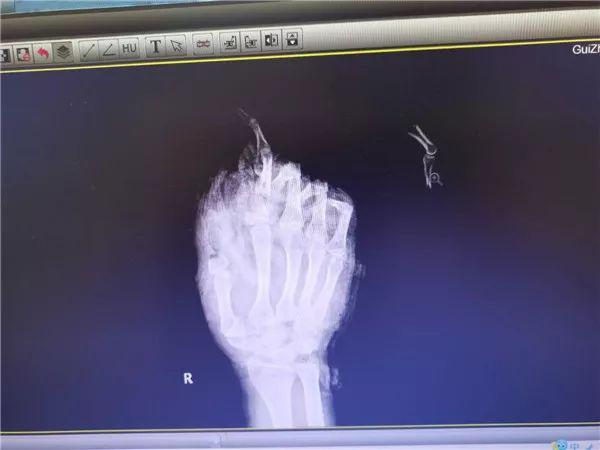

2 月 11 号下午两点,卢先生一家去上坟,他第一次点鞭炮以为没点着,再去点第二次时就不小心被炸伤了。" 当时血肉模糊,整个掌骨全部脱骨,手掌里面都没有肉了,我当时都要吓晕了," 回忆丈夫受伤的情景,岑女士还是很后怕。

目前卢先生已经完成初步接骨复位,等待一段观察期后还要进行第二次手术。